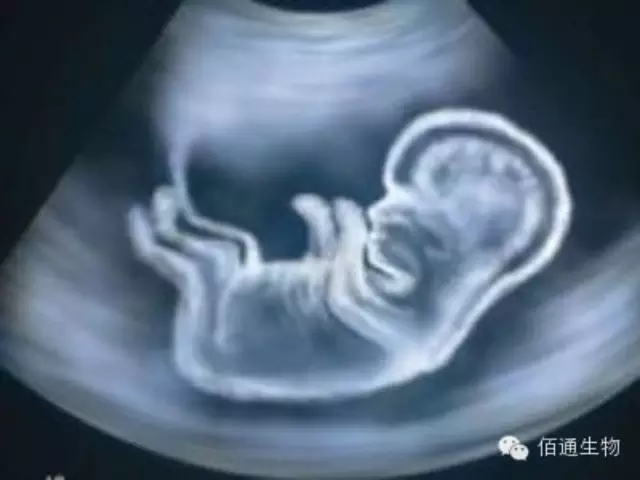

据科技资讯网站techinsider 8月6日报道,当夫妻二人决定要孩子时,他们将决定传递给一个婴儿的DNA,包括他们这一代人所有优点和缺点的基因。编辑新基因的工具将赋予我们直接绘制基因蓝图的能力。尽管“设计婴儿”饱受争议,有些人认为设计婴儿是完全合乎道德的,其过程是积极的,未来可能会成为准父母的一个很普通的决定,因为它能去除一些缺陷基因,甚至调整这些代码,加入一些疾病的抗体或者肌肉的优秀基因。

而现在,世界上大多数人对这一点非常怀疑。中国的研究人员发表了一篇论文,显示他们已经成功的编辑人类胚胎的基因,绝大多数人都谴责了这一行为。一些人批评了这个小组的科学素质:研究人员的工作中出现了许多意料之外和不需要的结果,以至于很多人以此为由,认为我们不应该在人类胚胎中应用这种技术,因为这些偏离目标的结果可能造成致命的或者削弱人类的突变。

其他人将这项工作视为可怕的征兆,预示着黑暗的未来:这些胚胎是无法存活的,意味着他们永远无法成为真正的婴儿。一个进行了这样的操作的胚胎,被移植和培育,不仅会影响这个胚胎培育成的个体,这些修改后的基因也会传递到其他胎儿身上,这些“设计婴儿”将塑造出人类的进化的方向。 由于这些原因,波士顿大学的生物伦理学家George Annas认为,“人们都不应该赞同设计婴儿。”